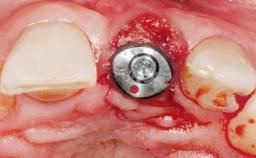

Late Placement of an Implant in a Maxillary Left Central Incisor Site

Type of Implants Two-Piece

Soft Tissue Grafting Simultaneous

Abutment Type Customized

Provisional Implant-Supported Prosthesis Prosthodontic margin < 3 mm apical to mucosal margin Prosthodontic margin < 3 mm apical to mucosal margin